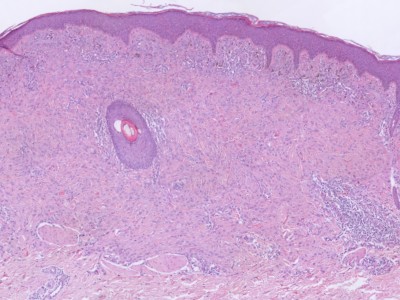

PA: Het karakteristieke PA kenmerk van Spitz tumoren

is de aanwezigheid van grote

spoelvormige cellen en/of

epithelioide cellen (melanocyten die lijken op keratinocyten).

Deze cellen zijn meestal gelegen in nesten hoog in de dermis, soms in de retelijsten

van de epidermis, soms in allebei. Er zijn verschillende histologische en morfologische

varianten van Spitz naevi, afhankelijk van welke chromosomale afwijking (tyrosine

kinase fusies, HRAS of MAP3K8 mutaties) er aanwezig is. Zie voor de correlatie

tussen de genetische afwijking, de klinische presentatie, en het histologisch

beeld het overzichtsartikel van Urso C. uit 2023.

De klassieke benigne

Spitz naevi zijn scherp begrensde symmetrische wigvormige laesies opgebouwd

uit grote junctionele (op de overgang epidermis-dermis) en dermale nesten van

spoelvormige en/of epithelioide melanocytaire cellen. Deze cellen zijn groot,

met veel bleek of matglas-achtig aankleurend cytoplasma en soms fijnkorrelig

pigment. Er is wat kern pleomorfisme, maar weinig of geen mitosen. De junctionele

nesten zijn loodrecht op de epidermis georiënteerd en vaak omgeven door spleetvormige

ruimten, dit zijn artefacten die ontstaan tijdens de bewerking van de coupe.

Melanocyten kunnen opstijgen in de epidermis (ascensie, synoniem pagetosis,

pagetoide verspreiding), meestal beperkt tot de onderste helft van de epidermis,

en transepidermale elininatie van melanocyten komt voor. Op de dermo-epidermale

overgang kunnen bij klassieke Spitz-naevi PAS-positieve eosinofiele hyaline

globuli voorkomen die

Kamino bodies worden genoemd.

Verder is er soms een perivasculair lymfocytair infiltraat. Zie ook de

ingescande

PA-coupe van de

afdeling

pathologie van de University of Toronto, en de ingescande coupes uit het

LUMC hier onder: